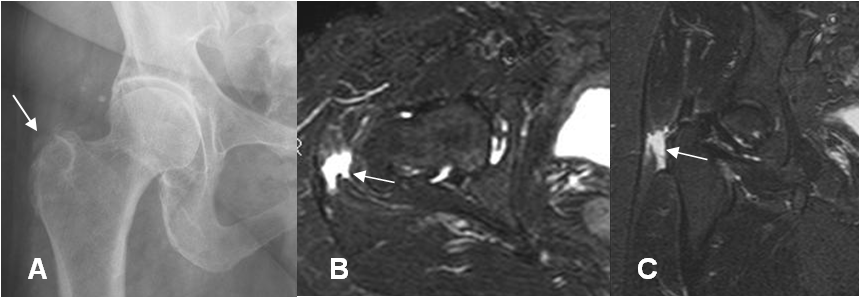

Fig 139. Bursitis.

A: Rx AP. Calcificación proyectada por encima del trocánter mayor.

B: RM axial y C: RM coronal en STIR. Líquido rodeando la parte lateral del trocánter mayor, por bursitis.